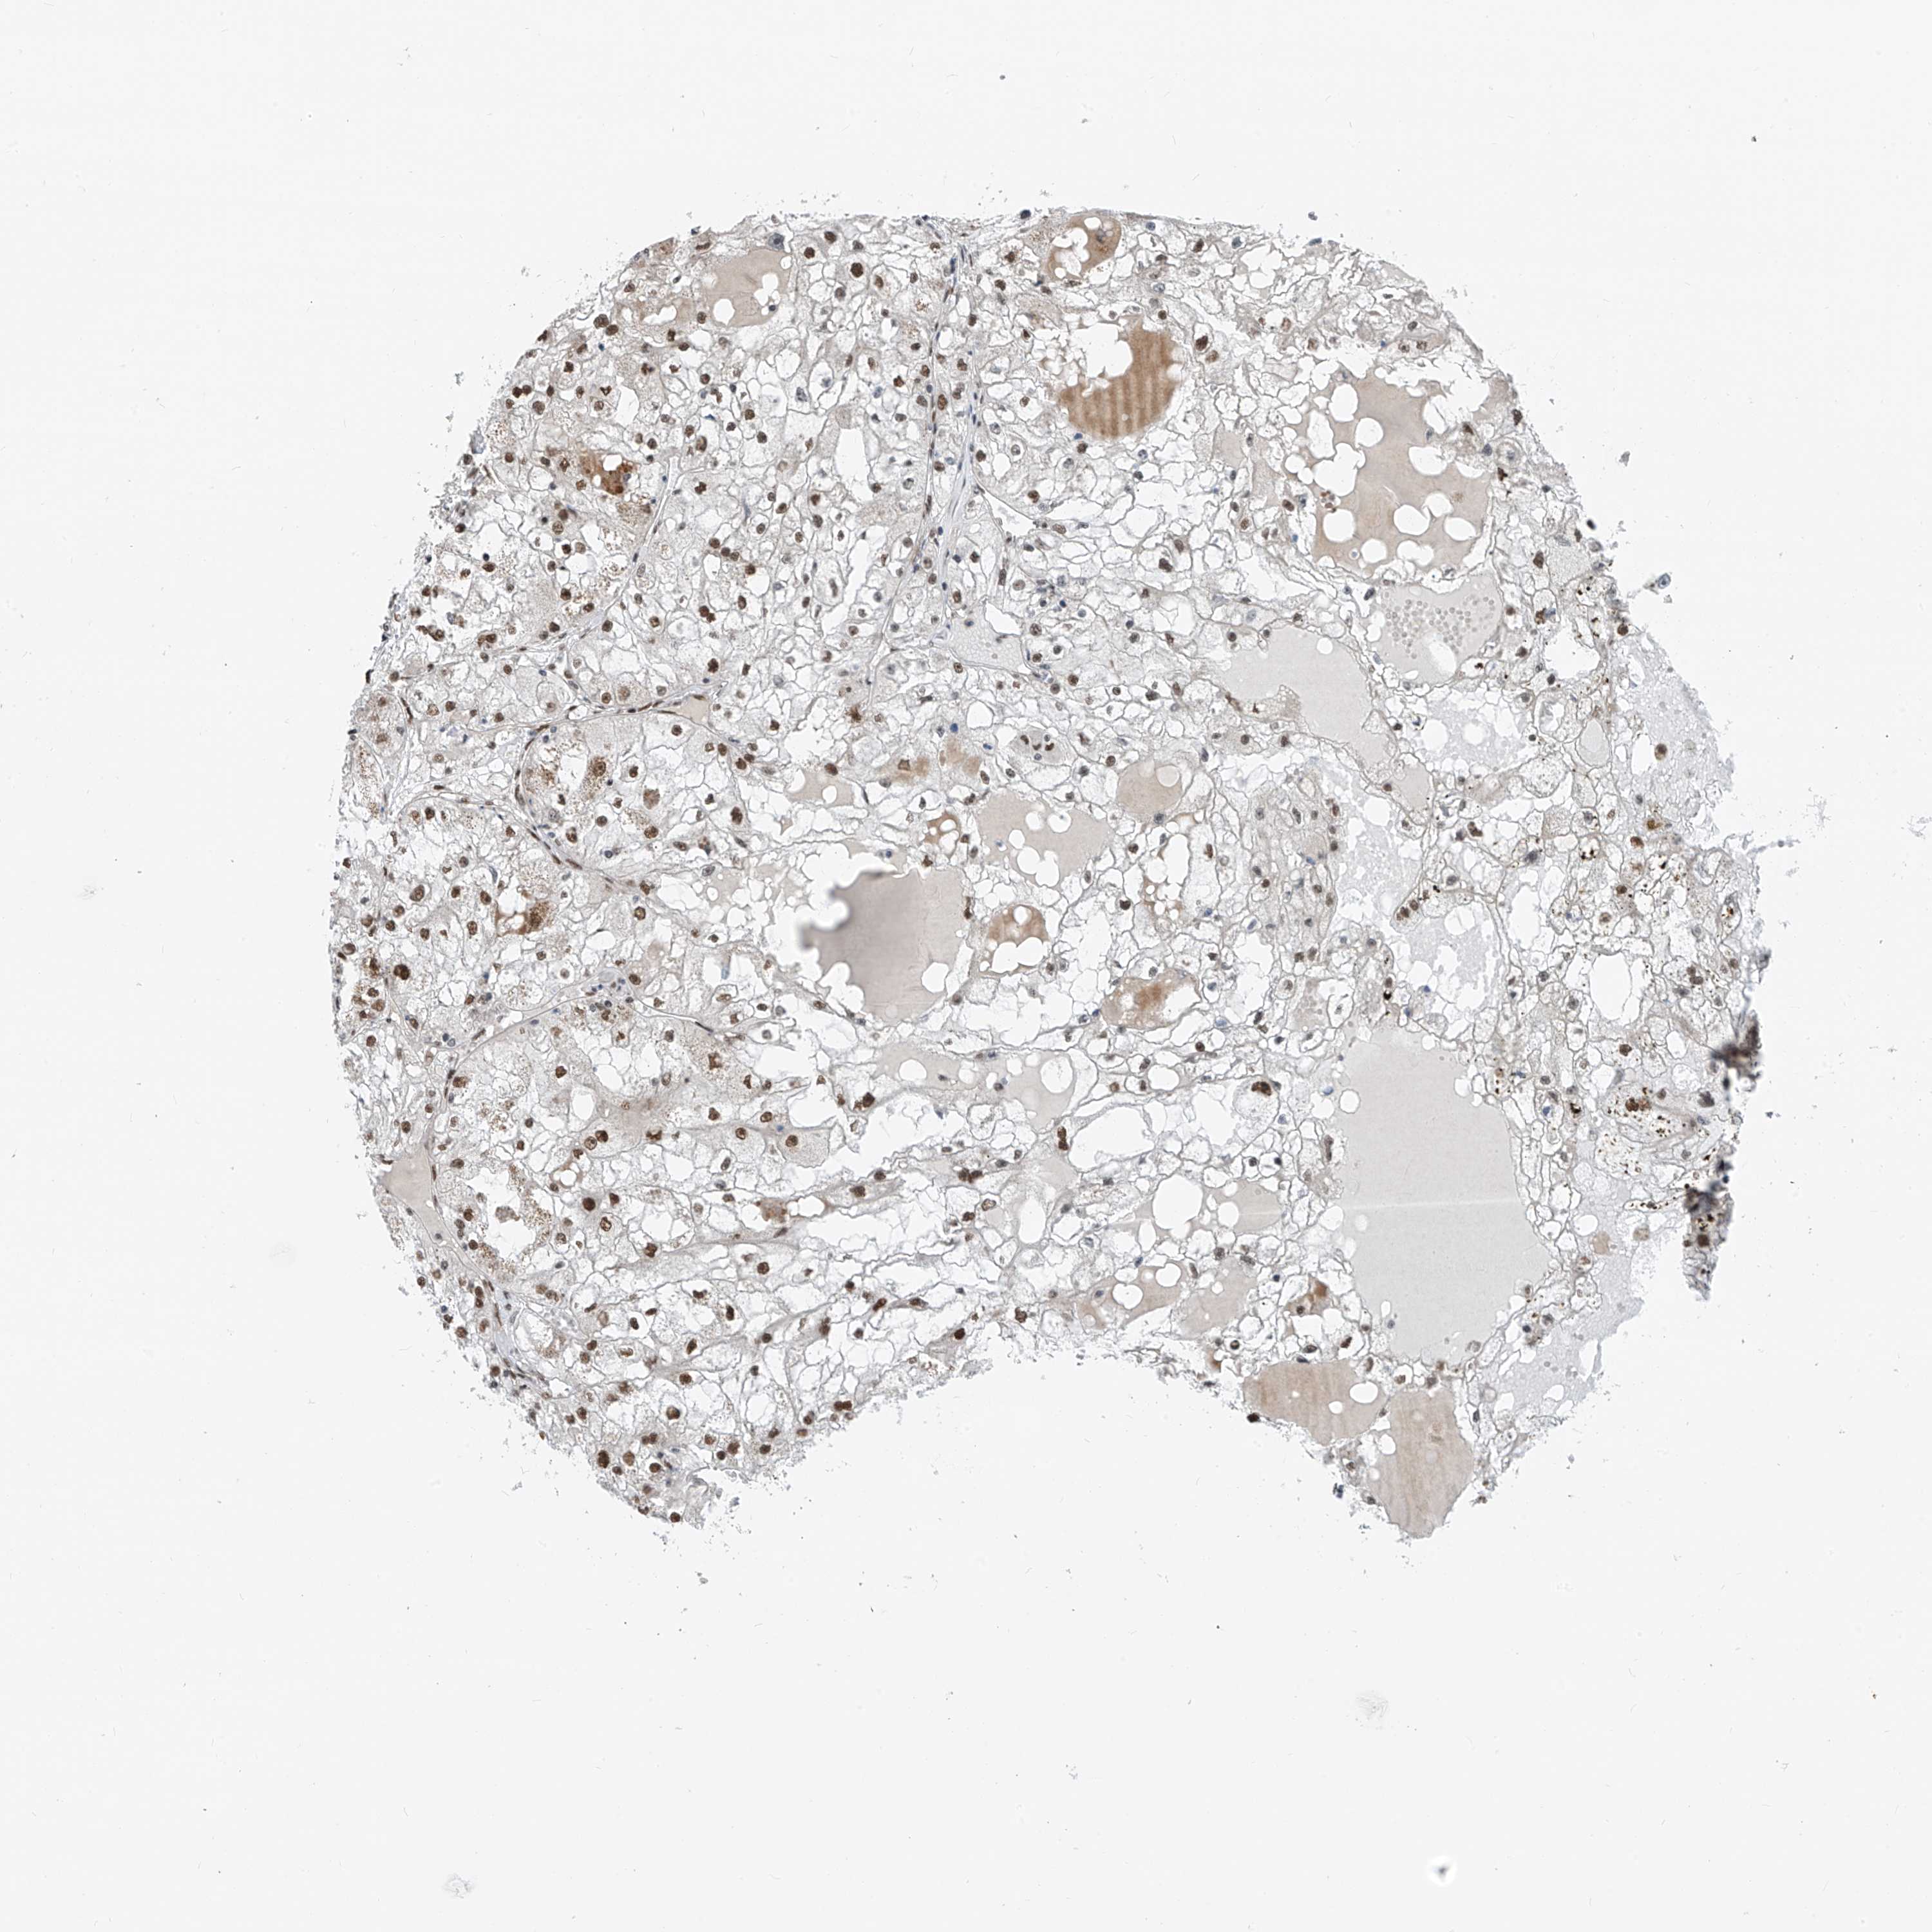

KIDNEY RENAL PAPILLARY CELL CARCINOMA (TCGA) - Interactive survival scatter ploti

The Survival Scatter plot shows the clinical status (i.e. dead or alive) for all individuals in the patient cohort, based on the same data that underlies the corresponding Kaplan-Meier plots. Patients that are alive at last time for follow-up are shown in blue and patients who have died during the study are shown in red.

The x-axis shows the expression levels (FPKM) of the investigated gene in the tumor tissue at the time of diagnosis. The y-axis shows the follow-up time after diagnosis (years). Both axes are complimented with kernel density curves demonstrating the data density over the axes. The top density plot shows the expression levels (FPKM) distribution among dead (red) and alive patients (blue). The right density plot shows the data density of the survived years of dead patients with high and low expression levels respectively, stratified using the cutoff indicated by the vertical dashed line through the Survival Scatter plot. This cutoff is automatically defined based on the FPKM cutoff that minimizes the p-score. The cutoff can be changed by dragging the vertical line or by entering a cutoff value in the square labeled "Current cut-off".

Under the Survival Scatter plot the p-score landscape (black curve; left axis) is shown together with dead median separation (red curve; right axis). Dead median separation is the difference in median mRNA expression between patients who have died with high and low expression, respectively. It is calculated as follows: median FPKM expression of dead patients with high expression - median FPKM expression of dead patients with low expression. This is intended to aid the user in visually exploring custom cutoffs and the associated p-scores and dead median separation.

Individual patient data is displayed and can be filtered by clicking on one or more of the category buttons on the top of the page. Categories describing expression level and patient information include: high, low, alive, dead, female, male and tumor stages. The scale of the x-axis can be toggled between linear and log-scale by clicking on the "x log" button. Mouse-over function shows TCGA ID, patient information and mRNA expression (FPKM) for each patient.

& Survival analysisi

Kaplan-Meier plots summarize results from analysis of correlation between mRNA expression level and patient survival. Patients were divided based on level of expression into one of the two groups "low" (under cut off) or "high" (over cut off). X-axis shows time for survival (years) and y-axis shows the probability of survival, where 1.0 corresponds to 100 percent.

RBP7 is not prognostic in Kidney Renal Papillary Cell Carcinoma (TCGA)